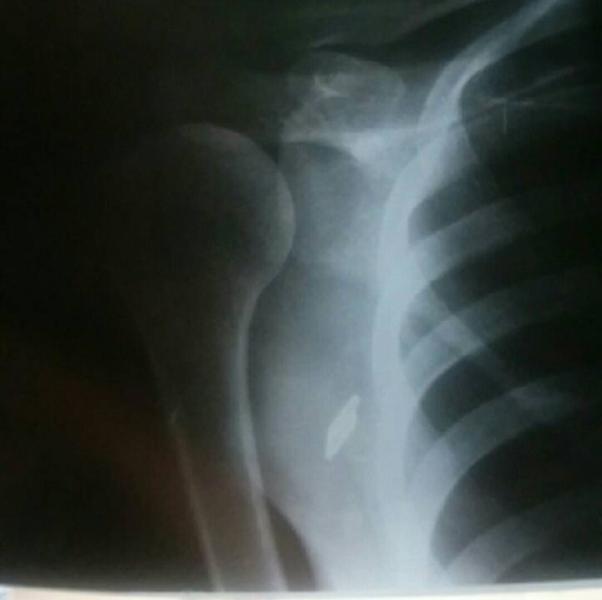

девочки, кто может разбирается в снимках рентгеновских? болит третий день под ключицей и отдает в плечо и шею... сегодня очень сильно разболелось и печет целый день, пришлось бабушку вызывать для помощи с ребенком. Сделала снимок а на расшифровку не успела сдать... спасибо🙏

@aburchakova а вот так вот у нас! снимок сделали и сказали нести к врачу рентгенологу на описание

@aburchakova я сегодня целый день по врачам и узи и терапевты и неврологи платные. единственное что не успела описание сделать это описание снимка в бесплатной поликлинике